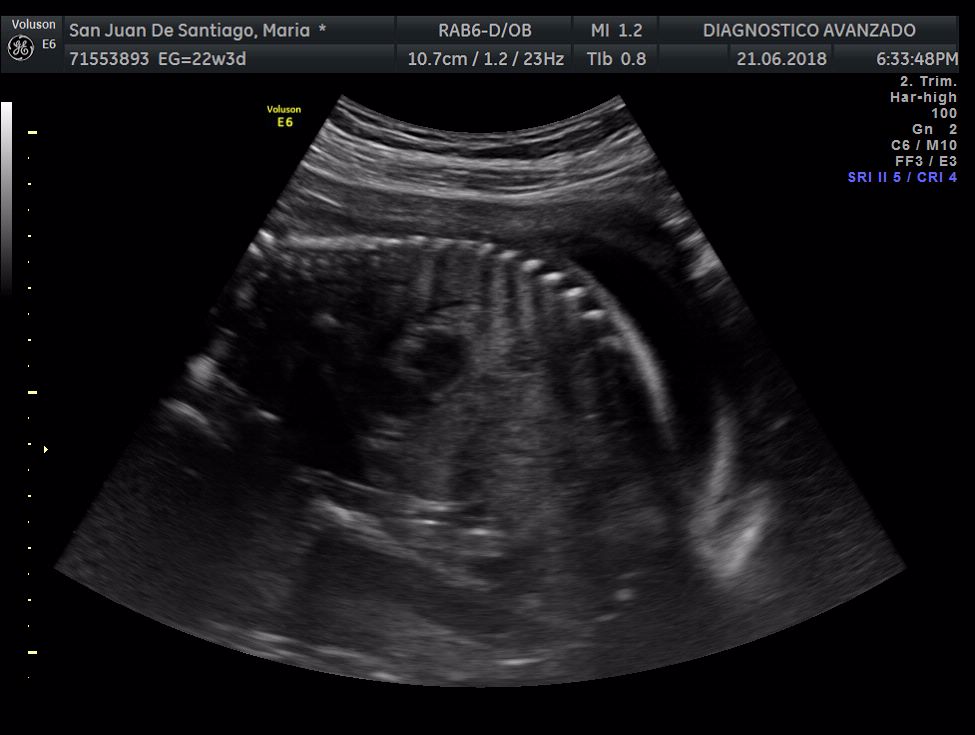

¡Hola a todos! Hoy hemos ido a hacer la tradicional ecografía 3D de la niña, os dejamos todo el material (aunque es un poco demasiado).